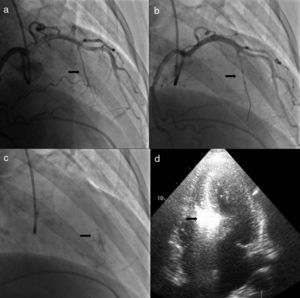

O procedimento descrito tem com certeza pequenas diferenças em relação ao usado por outros centros e operadores, embora os passos fundamentais sejam comuns a todos que privilegiem uma técnica segura. Queremos destacar três alterações que contribuíram para um aumento da sua segurança e para a melhoria dos resultados atuais face aos descritos nas primeiras séries de doentes. A primeira consiste na utilização de menor quantidade de álcool, diminuindo a área de necrose e com isso a possibilidade de afetar o tecido de condução auriculoventricular. Também a ideia de ter um objetivo imediato de redução do gradiente, repetindo as injeções de álcool se necessário, foi abandonada a favor da avaliação dos resultados após a cicatrização e remodeling do septo. A segunda foi introduzida por Faber em 1998, quando utilizou a injeção de contraste intramiocárdio e a ecocardiografia transtorácica para identificar corretamente a artéria septal alvo e excluir a afetação de regiões remotas do miocárdio14. Este é atualmente um passo de grande relevância no procedimento, como exemplifica a nossa experiência em que a artéria alvo foi modificada em 10% dos doentes (Figura 2), sendo que em três doentes (não incluídos nesta população) a intervenção foi abandonada por não existir uma septal alvo em função da informação ecocardiográfica. Por fim, a introdução de scores de risco para o estabelecimento do bloqueio da condução auriculoventricular de alto grau veio permitir distinguir os doentes em que é correto aguardar pela resolução da fase de edema do septo, após a qual se assiste na maioria dos casos à resolução da perturbação da condução, daqueles em que se deve optar logo pela colocação de pacemaker definitivo13.

Alteração da septal alvo após injeção de contraste intracoronário. a) Cateterização seletiva da segunda septal. b) Cateterização selectiva da primeira septal. c) Opacificação da parte direita do septo após injeção de contrate na segunda septal. d) Opacificação da região adequada do septo, porção basal em relação com o folheto anterior da válvula mitral, com injeção de contraste na primeira septal.